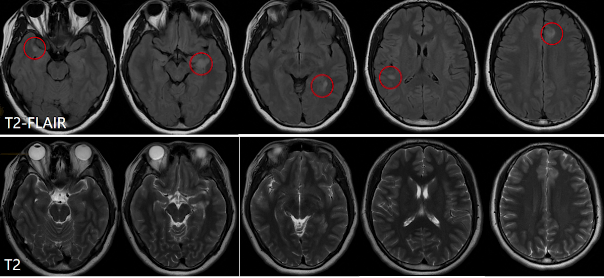

影像学检查方面,头颅MRI平扫显示,在FLAIR序列上,右侧颞叶、左侧海马旁回及左侧额叶均有病灶,呈T2-FLAIR高信号、T2稍高信号,病变位于皮层及近皮层区域。

(一)颅内病灶分析

·疾病数目:NMOSD、MOGAD及ADEM均为多发病灶,无法区分。

·病变位置:NMOSD多位于脑室周围、下丘脑、脑干背侧及胼胝体,与本病例不符;MS常见于脑室周围,也可位于皮质及近皮质区域,本病例符合;ADEM位于深部白质、基底节、丘脑、脑干,与本病例不符。

·病灶形态:MS幕上病变体积大、云雾状与本病例不符,位于脑室周围时的直角脱髓鞘征及Dawson指征本病例未出现,但位于皮质及近皮质区域时呈卵圆形与本病例相符;ADEM呈斑片状,边界模糊,垂直中线,T2及FLAIR序列高信号,且有坏死及小出血灶。

·强化特点:急性期均有强化,缓解期无明显强化。

结合颅内及髓内病灶分析,该病例从影像学上初步倾向于MS。

综合影像分析及临床特点补充,影像学诊断为多发性硬化。回顾病灶特点,颅内病灶多发,经典部位在脑室周围,也可位于皮质及近皮质区域,脑室周围可表现为直角脱髓鞘病灶、Dawson手指征及卵圆形,T2和T2 FLAIR高信号,增强扫描可强化;髓内病灶位于侧索,局灶性、短节段,T2高信号,急性期有强化。临床特殊检查结果显示血的AQP4阴性,脑脊液的寡克隆区带阳性,最终临床结合病史及检查,诊断为复发缓解型多发性硬化。